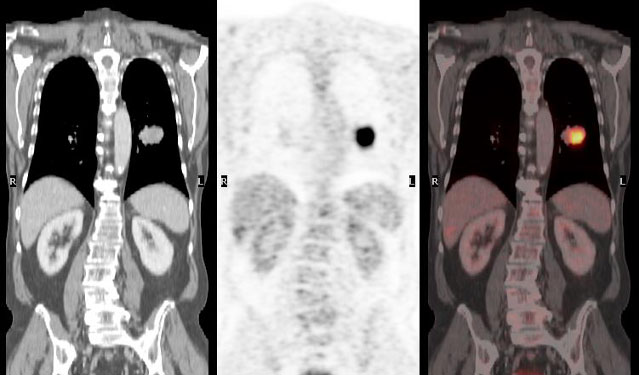

Onkologische Bildgebung

Das gesamte Spektrum der bildgebenden Verfahren bei Krebserkrankungen, von der ersten Diagnostik bis zu Kontrolluntersuchungen nach überwundener Krebserkrankung.

Alle bösartigen Erkrankungen (Krebs)

Die Onkologie ist das Fach in der Medizin, welches sich mit der Diagnostik und der Therapie von Krebserkrankungen beschäftigt. In der Radiologie und Nuklearmedizin befasst sich die onkologische Bildgebung mit dem gesamten Spektrum der bildgebenden Verfahren bei Krebserkrankungen, von der ersten Diagnostik bis zu Kontrolluntersuchungen nach überwundener Krebserkrankung.

Über 230.000 Menschen sterben in Deutschland im Schnitt pro Jahr an einer Krebserkrankung. Die häufigsten Todesursachen unter den Krebserkrankungen sind bei Frauen Brustkrebs/Mamma-Karzinom (17 Prozent aller krebsbedingten Sterbefälle), gefolgt von Lungenkrebs (16 Prozent) und Darmkrebs (10 Prozent). Bei Männern ist hingegen Lungenkrebs für 22 Prozent der Krebssterbefälle verantwortlich, gefolgt von Prostatakrebs (12 Prozent) und Darmkrebs (10 Prozent). Schaut man sich die Entwicklung im längeren Verlauf an, sind seit 2010 die altersstandardisierten Sterberaten an Krebs bei den Frauen um 7 Prozent und bei den Männern um 12 Prozent zurückgegangen.

Trotzdem gehören Krebserkrankungen immer noch zu den Krankheiten, welche bei den meisten Patientinnen und Patienten große Ängste und Unsicherheiten hervorrufen, welche aber aufgrund des Fortschritts in der Medizin nicht mehr zwangsläufig die Lebenszeit verkürzen. Hierzu trägt auch die moderne Radiologie und Nuklearmedizin mit den verbesserten Methoden zur (Früh-)Erkennung und Verlaufsbeurteilung von Krebserkrankungen bei. Wir bieten Ihnen als Gemeinschaftspraxis das gesamte Spektrum der onkologischen Bildgebung in der Radiologie und Nuklearmedizin vom Röntgenbild bis zum PET-CT an.